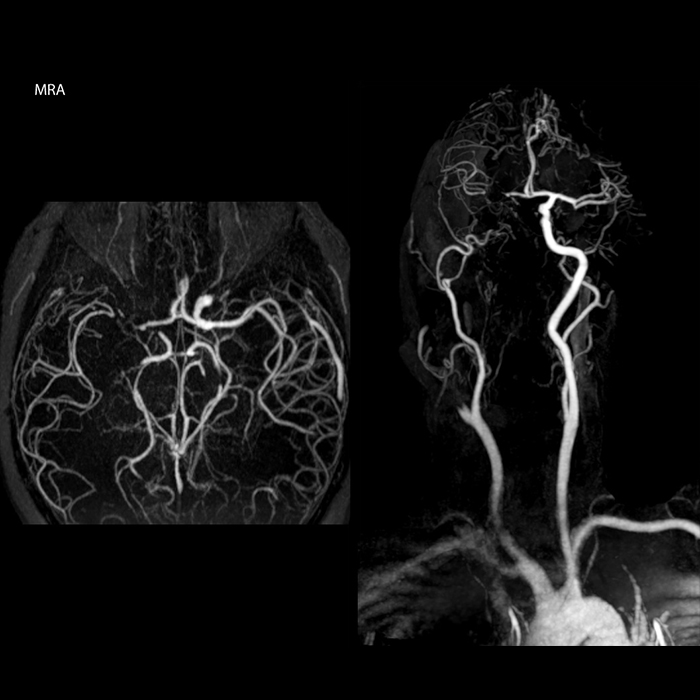

„In Frankreich werden Schlaganfälle in der Regel per MRT und nicht per CT untersucht, auch bei der Notfallbehandlung.“ „In Frankreich erfolgt die Bildgebung bei Schlaganfällen in der Regel per MRT, nicht per CT, auch bei der Notfallbehandlung. Das liegt daran, dass wir mit der MRT eine Ischämie in der akuten Phase direkt darstellen, aber auch Differenzialdiagnosen wie MS und Hämatom ausschließen können. Außerdem ist es uns möglich, die intrakraniellen und extrakraniellen Gefäße im Laufe derselben Untersuchung zu beurteilen“, sagt Dr. Savatovsky.

„Ingenia bietet eine große Flexibilität bei der Parametereinstellung, d.h., wir können eine Sequenz beliebig abstimmen“, erklärt Dr. Savatovsky. „Bei einer Schlaganfalluntersuchung nutzen wir zum Beispiel eine FLAIR-Sequenz von etwa zwei Minuten anstelle der vierminütigen Sequenz, die wir bei MS verwenden. Die Diffusionsbildgebung dauert 30 Sekunden, der T2*-gewichtete Scan ebenfalls 30 Sekunden und die Scan-Dauer bei der Angiographie beträgt weniger als eine Minute. Ingenia ist in dieser Situation ein großartiger Scanner. Auch bei diesen schnellen Sequenzen erzielen wir hochwertige Bilder mit einem guten Signal-Rausch-Verhältnis. Wenn wir anhand der ersten Sequenz feststellen, dass es sich nicht um einen ischämischen Schlaganfall, sondern um einen hämorrhagischen Schlaganfall handelt, können wir zu einer zeitaufgelösten Angiographie wechseln, um nach vaskulären Malformationen und einer Venenthrombose zu suchen.“

„Jede Klinik arbeitet anders, aber für mich umfasst das ideale Schlaganfallprotokoll die diffusionsgewichtete Bildgebung, die FLAIR- und die schnelle suszeptibilitätsgewichtete Bildgebung“, sagt Dr. Savatovsky. „Unsere schnelle suszeptibilitätsgewichtete Bildgebung dauert nur 50 Sekunden, sie ist also genauso schnell wie die T2*-gewichtete Bildgebung. Damit werden Blutungen, aber auch Koagulationen dargestellt. Wir führen zusätzlich eine 3D-MR-Angiographie durch, die Informationen über zervikale und zerebrale Gefäße liefert. Wenn die Patienten keine sofortige Behandlung benötigen oder wenn zusätzliche Informationen erforderlich sind, um über die Therapie zu entscheiden, nehmen wir außerdem eine Perfusionsbildgebung und eine T1-gewichtete Postkontrastbildgebung vor.“